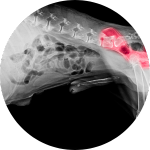

Arthrose ist eine schmerzhafte Erkrankung der Gelenke, die bei Hunden häufig vorkommt. Es gibt verschiedene Ursachen, die dazu führen können, dass Hunde an Arthrose erkranken.

Arthrose äußert sich durch Gelenkschmerzen, die ein Hund durch Hinken, Steifheit und Lahmheit zeigen kann.

Ein weiteres Symptom ist eine eingeschränkte Beweglichkeit des Gelenks sowie Schmerzen bei Berührung oder Druck auf das Gelenk.